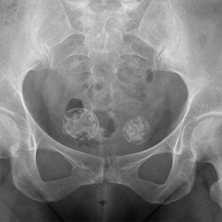

(Слева) КТ, корональный срез: у мужчины 57 лет с повышенным гематокритом определяется спленомегалия и диффузный склероз костей таза, позвоночника и проксимального отдела бедренной кости.

(Справа) КТ, корональный срез: у этого же пациента на срезе чуть долее кпереди можно оценить выраженность гепатоспленомегалии. Наблюдается диффузный склероз таза без утолщения кортикальной пластинки. Эти признаки характерны для миелофиброза, причиной которого в этом случае является истинная полицитемия. (Слева) КТ, аксиальный срез, этот же пациент: диффузный и, в некоторой степени, пятнистый склероз без изменения размеров костей или кортикальной пластинки, что характерно для миелофиброза.